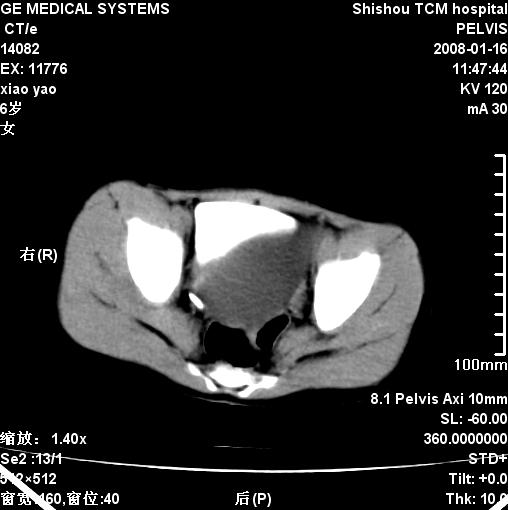

女,6岁,因腹痛做b超检查发现囊性包块.

盆腔内囊性占位性病变——脐尿管囊肿?

盆腔内囊性占位性病变,小小年纪,脐尿管囊肿可能性最大。

盆腔内囊性占位性病变——脐尿管囊肿

盆腔内囊性占位性病变——脐尿管囊肿。